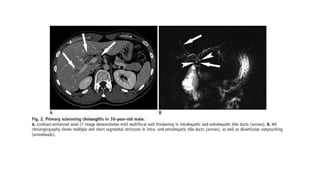

Primary Sclerosing Cholangitis

Primary sclerosing cholangitis is a chronic, progressive liver disease with inflammation and

fibrosis of the bile ducts of unidentified etiology, which finally progresses to biliary cirrhosis and

portal hypertension

• PSC affects men twice as often as women, and generally young patients with an age of onset

of 30–40 years. PSC has a strong association with inflammatory bowel diseases

• The clinical presentation can vary, including cholestatic laboratory findings and nonspecific

symptoms including right upper quadrant pain or jaundice.

• The typical MR cholangiographic features include diffuse, multifocal short segmental

strictures and mild dilatation in the intrahepatic and extrahepatic bile ducts alternating with

normal ducts, which sometimes produce “beaded” appearance .As the fibrosis progresses and

strictures worsen, the peripheral bile ducts are obliterated and become poorly visualized on

MR cholangiography showing a “pruned tree” appearance . Diverticular outpouching of bile

ducts is another characteristic finding that occurs in up to 27% of the patients with PSC

(Almost half of patients with PSC have some degree of mural irregularity causing a shaggy or

nodular appearance of the bile ducts . PSC commonly involves both intrahepatic and

extrahepatic ducts in 75% of patients, whereas involvement of only the extrahepatic bile duct

is uncommon (10% of patients) and isolated involvement of the intrahepatic bile ducts is

reported in 15% of patients

• Abdominal ultrasonography (US) is generally non-diagnostic, although thickened or focal

dilated bile ducts are observed in PSC patients. Computed tomography (CT) demonstrates

alternating narrowing and dilatation of the bile ducts with contrast enhancement in PSC . CT

and MR imaging also show associated parenchymal changes of the liver, as well as ductal

changes in PSC. A rounded liver appearance is observed due to hypertrophy of the caudate

lobe and atrophy of the left lateral and right posterior segments in PSC .

• In PSC, T2-weighted MR images show a wedge-shaped or reticular heterogeneous area of

high-signal intensity with peripheral distribution .

Primary Sclerosing Cholangitis Primarysclerosing cholangitis is a chronic, progressive liver disease with inflammation and fibrosis of the bile ducts of unidentified etiology, which finally progresses to biliary cirrhosis and portal hypertension • PSC affects men twice as often as women, and generally young patients with an age of onset of 30–40 years. PSC has a strong association with inflammatory bowel diseases • The clinical presentation can vary, including cholestatic laboratory findings and nonspecific symptoms including right upper quadrant pain or jaundice. • The typical MR cholangiographic features include diffuse, multifocal short segmental strictures and mild dilatation in the intrahepatic and extrahepatic bile ducts alternating with normal ducts, which sometimes produce “beaded” appearance .As the fibrosis progresses and strictures worsen, the peripheral bile ducts are obliterated and become poorly visualized on MR cholangiography showing a “pruned tree” appearance . Diverticular outpouching of bile ducts is another characteristic finding that occurs in up to 27% of the patients with PSC (Almost half of patients with PSC have some degree of mural irregularity causing a shaggy or nodular appearance of the bile ducts . PSC commonly involves both intrahepatic and extrahepatic ducts in 75% of patients, whereas involvement of only the extrahepatic bile duct is uncommon (10% of patients) and isolated involvement of the intrahepatic bile ducts is reported in 15% of patients

• Abdominal ultrasonography(US) is generally non-diagnostic, although thickened or focal dilated bile ducts are observed in PSC patients. Computed tomography (CT) demonstrates alternating narrowing and dilatation of the bile ducts with contrast enhancement in PSC . CT and MR imaging also show associated parenchymal changes of the liver, as well as ductal changes in PSC. A rounded liver appearance is observed due to hypertrophy of the caudate lobe and atrophy of the left lateral and right posterior segments in PSC . • In PSC, T2-weighted MR images show a wedge-shaped or reticular heterogeneous area of high-signal intensity with peripheral distribution . • Patients with PSC have a 10 to 15% risk of developing cholangiocarcinomas, and a 7 to 9% chance of a 10-year cumulative incidence of cholangiocarcinomas • Progressive ductal dilatation seen in follow-up studies, marked ductal dilatation, severe ductal narrowing, mural thickening, and intraductal polypoid lesions in PSC are also highly suggestive of cholangiocarcinoma